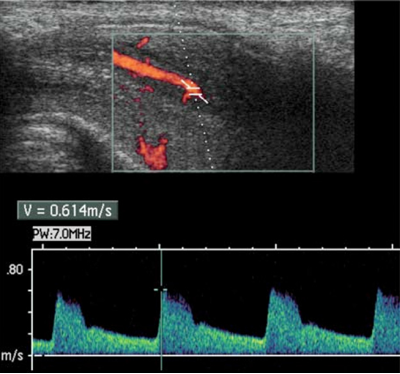

Tra gli esami di secondo livello attualmente è considerato “gold standard” per porre diagnosi di certezza di DE l’Eco-color-Doppler dinamico del pene (FIGURA 2), indicato per la valutazione dell’integrità vascolare del pene. Si tratta di uno studio dinamico, ossia funzionale, eseguito in condizioni di base e dopo stimolazione con farmaci iniettati all’interno del pene, per studiare l’afflusso ed il deflusso del sangue in condizione di erezione indotta farmacologicamente mediante sostanze vaso-attivo a dosaggio standardizzato (Alprostadil).

2 b: misurazione doppler del flusso arterioso

il flusso arterioso dell’arteria dorsale del pene viene identificato all’ecografia e l’ampiezza del flusso viene misurata mediante l’effetto doppler.

Color Doppler US of the Penis. M. Bertolotto (Ed.). Springer 2008. Pag 50 P Pavlica, M Valentino, L Barozzi